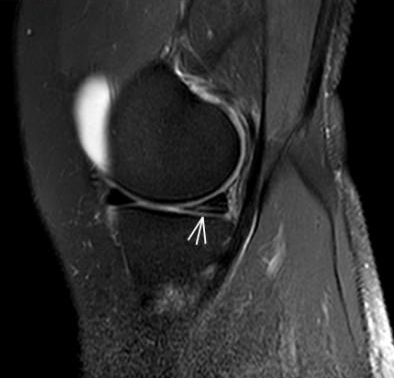

5. 夜间持续性钝痛——骨骼的“暗夜低语”

场景:无外伤却夜间痛醒,膝盖仿佛“压着巨石”

MRI侦查:筛查骨肿瘤、骨髓水肿(X线看不见的“内伤”),警惕“沉默杀手”

(骨髓水肿)